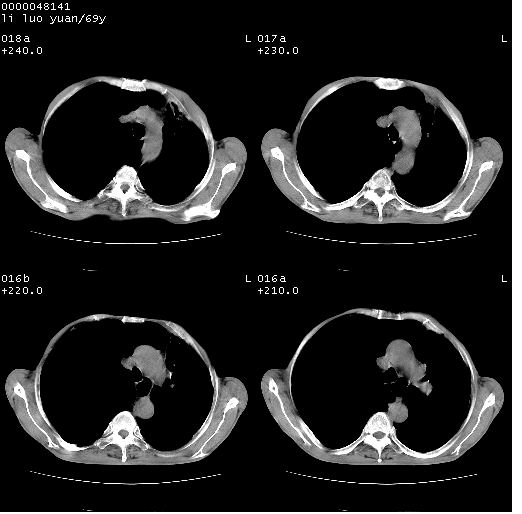

临床资料:老年患者,咯血、消瘦

影像表现:桶状胸,双肺纹理纤细、紊乱,透过度增高,肺野内可见多发、散在、大小不等的无壁高透过影,右肺中叶外侧段分叶样软组织占位,左上肺纤维索条样密度影,相应层面左侧胸腔轻度萎陷,纵隔左移。

影像诊断:1、慢支、肺气肿、双下肺野肺大泡形成

2、左上肺陈旧性肺结核

3、右肺中叶外侧段占位 考虑肺ca可能性较大、建议增强及痰检脱落细胞